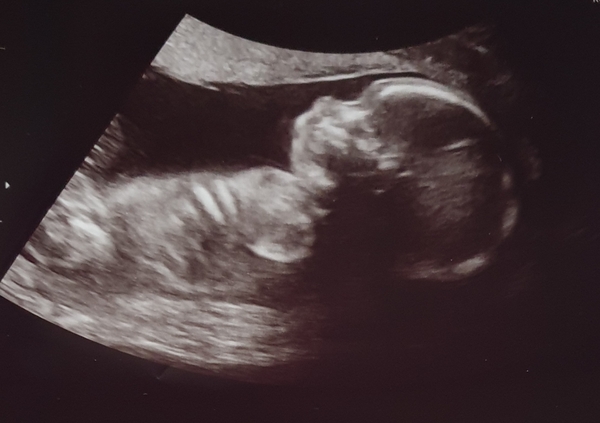

Sorry for the quick selfish post but wanted to share my 20 week scan pic with you all, all. Very positive scan really lovely lady doing the scan, everything is in the right place with all the right amount of bits and pieces!! And she's 80% sure we are having a little girl 😊

@Lozzak87 Brilliant news on the scan and what a lovely picture! Welcome to Team Baby Girl! Grin So exciting!

@Lozzak87 congratulations on the beautiful scan picture and that you are carrying a girl.

@Lozzak87 what a lovely scan picture! And a little girl potentially too! That has to balance this group out a bit I think? Feels boy heavy in here lately!